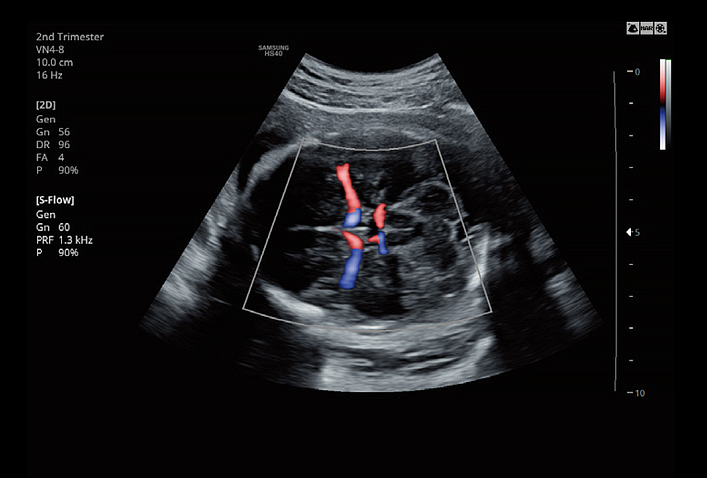

VN4-8Application:Abdomen, Obstetrics, Gynecology, Musculoskeletal, Pediatric, Vascular, Urology |